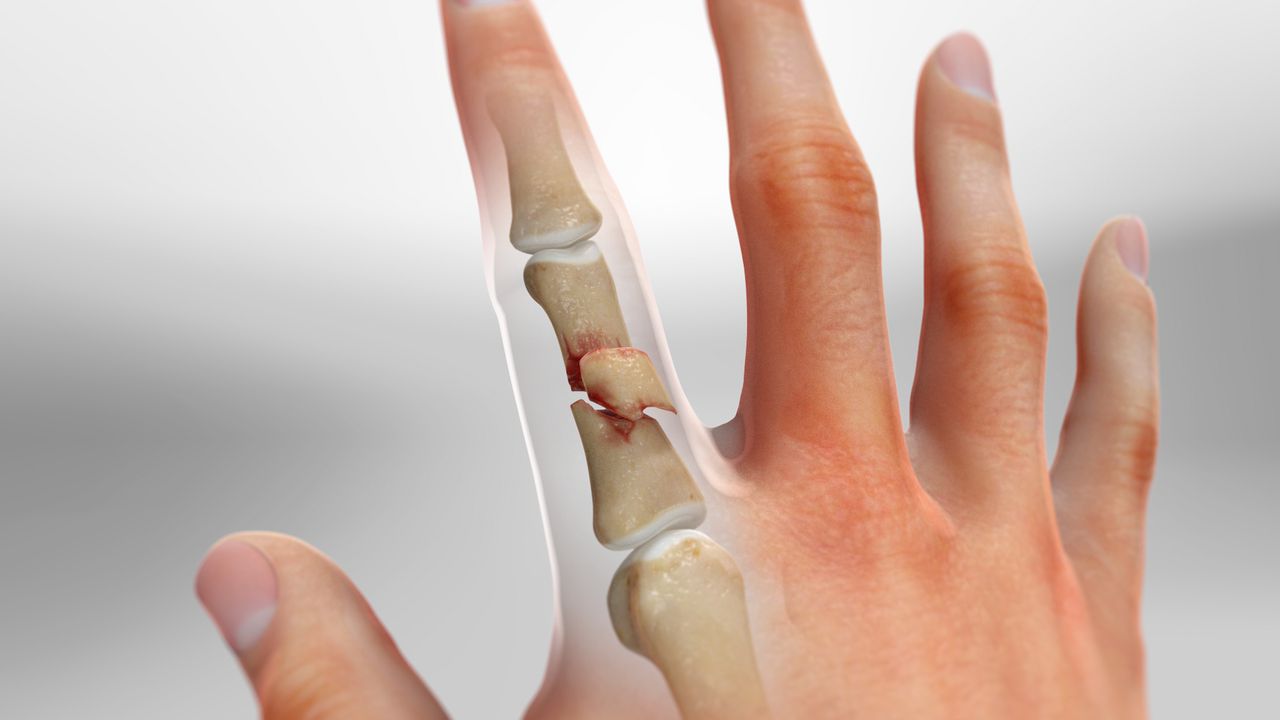

- 횡골절(Transverse fracture): 뼈가 수평 방향으로 부러져 평면이 단순한 형태.

- 사선·나선 골절(Oblique/Spiral fracture): 힘이 비스듬히 작용해 길게 갈라지는 형태.

- 분쇄 골절(Comminuted fracture): 강한 충격으로 두 조각 이상 파편화.

- 관절내 골절(Intra-articular fracture): 관절면까지 골절선이 침범해 향후 관절염 위험 ↑.

- 탈구 동반 골절(Fracture-dislocation): 골절과 함께 관절 위치가 어긋난 상태.